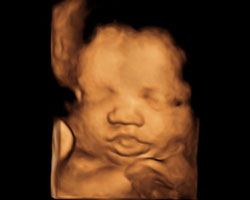

Nesta altura da gravidez, o teu bebé já não muda praticamente nada. De todos os modos, de certeza que queres ver como estará na 39ª semana, tanto em movimento como na ecografia. Aqui tens!

Ecografia de 39 semanas